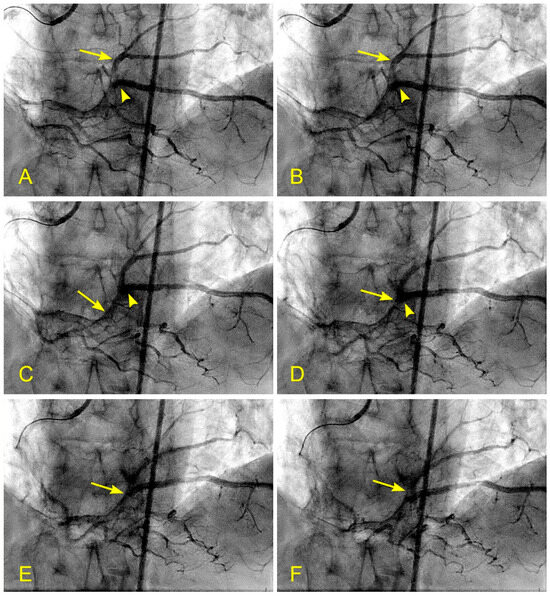

Figure 15.

(A–F) Reverse flow in distal right coronary artery. This is a series of six sequential images separated by 6 milliseconds each (15 images per second). (A) The blood, in white, moves forward to the distal right coronary artery (RCA) (arrow) past the origin of the posterior descending artery (PDA) (arrowhead). (B) The blood (white) is now clearly distal to the origin of the PDA (arrow), while the contrast at the origin of the PDA stays stagnant and homogenously black (arrowhead). (C) Flow reversal. At the beginning of systole, at the distal RCA, the contrast reverses its direction and flows back past the origin of the PDA (arrow). (D) At the distal RCA, the blood (in white) pushes back the contrast (arrow) in the antegrade direction. The flow reversal is short-lived. (E,F) At the distal RCA, the blood, in white, moves forward as usual (arrow). If the reversed flow had been strong and lasted longer, more damage could have been inflicted on the endothelium and could have triggered the atherosclerotic cascade.